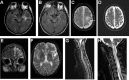

Characteristic MRI brain and spinal cord findings. A, T2 FLAIR axial of brain demonstrating left hippocampal T2 abnormality typical of limbic encephalitis, which resolved with immunotherapy, B. C, T2 FLAIR axial image of brain demonstrating a superior–posterior left frontal abnormality in a patient who presented with right upper extremity apraxia and myoclonus. D, Postimmunotherapy improvement. E, T2 coronal FLAIR demonstrated extensive, predominantly left frontal cortical abnormality in a patient with ANNA-1 (anti-Hu), also seen on T2 axial image F. G, Sagittal T2 MRI of spinal cord demonstrates longitudinally extensive myelitis typical of NMO. H, Sagittal T2 MRI image of a patient with NMO who presented with intractable vomiting and myelitis. The longitudinally extensive lesion extends into the brain stem. Reproduced with permission from American Medical Association (C-F) and Lippincott Williams & Wilkins (H). MRI indicates magnetic resonance imaging; NMO, neuromyelitis optica; ANNA, antineuronal nuclear antibody.